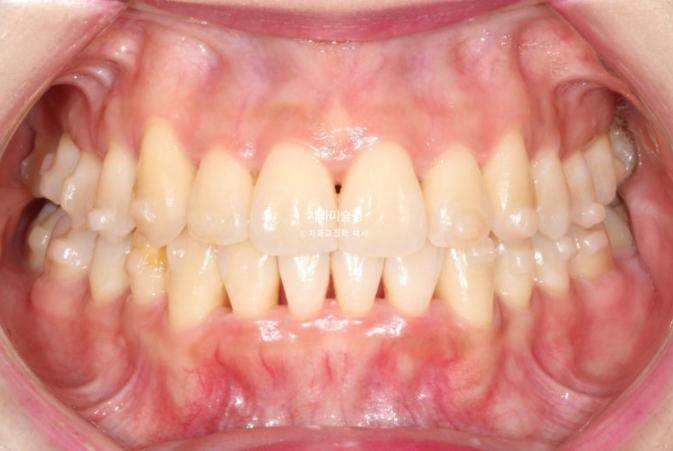

이제 전후비교 보겠습니다.

23.08~25.10

상악 제2대구치 발치공간을 이용하여 송곳니 덧니를 배열했습니다.

사랑니는 발치한 두 번째 큰어금니 자리를 잘 채워주고 있습니다.

하악 사랑니 공간을 이용하여 덧니를 배열했습니다.

중심선의 개선, 과개교합의 개선, 덧니의 개선, 블랙트라이앵글의 개선이 보입니다.

앞니는 뒤로 들어가지도, 나오지도 않고 잘 유지되었습니다.